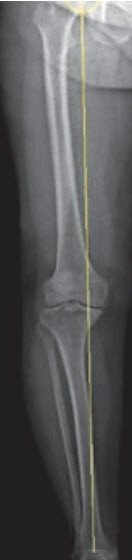

Arthrosebedingte Beinachsenabweichungen wie X- oder O-Beine werden während der Operation teilweise korrigiert.